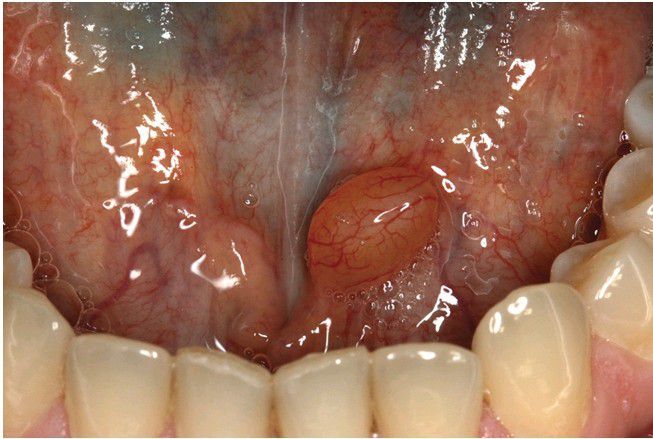

Salivary Duct Cyst.

Nodular swelling overlying Wharton duct.